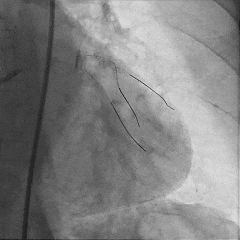

Sion导丝至LCX远端,预扩球囊扩张后,植入支架XIENCEAlpine 2.25*23mm支架一枚

术后造影支架膨胀良好,血流TIMI3级